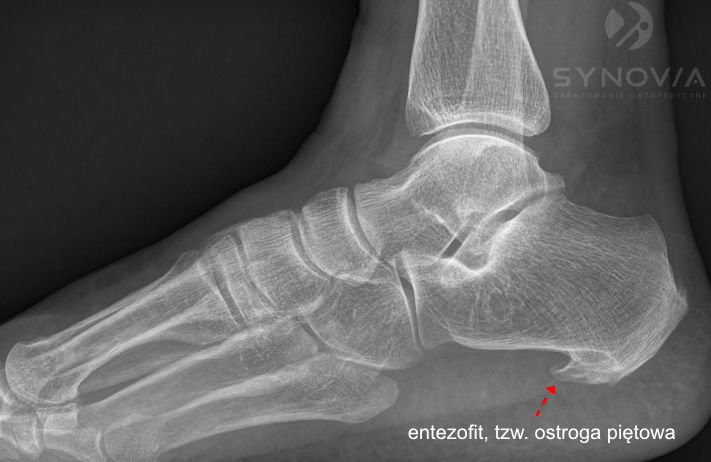

RTG

Co widać: Ostroga piętowa – kostny wyrostek w miejscu przyczepu powięzi. Obecna również u wielu bezobjawowych osób.

Ważna informacja: Ostroga piętowa jest obecna u około 50% osób bezobjawowych, a jej obecność nie koreluje bezpośrednio z nasileniem dolegliwości. To stan tkanek miękkich, nie sama ostroga, jest źródłem bólu, dlatego samo RTG nie wystarczy do postawienia diagnozy.

Co widać: Entezofity – kostne wyrostki w miejscu przyczepu, ewentualnie nadżerki kości (w chorobach reumatycznych).